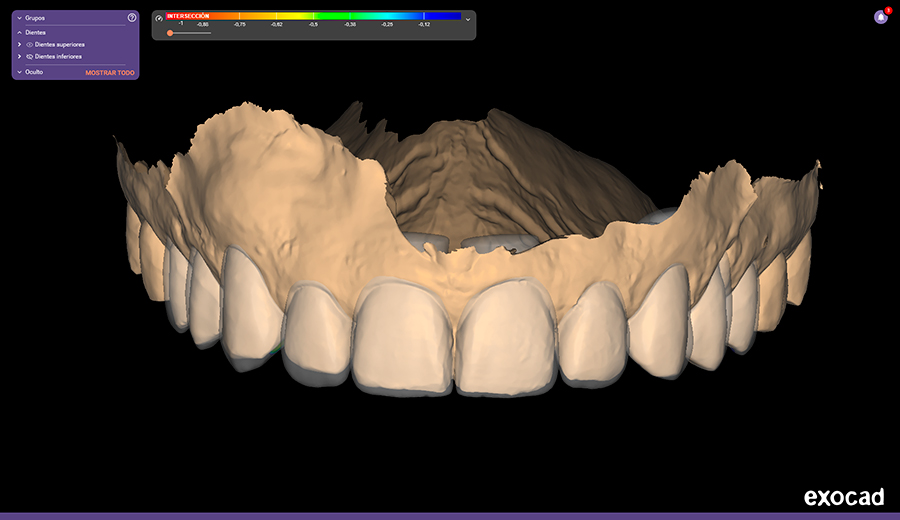

- Análisis facial y dental: Mediante software específico, se estudian proporciones, ejes dentales, simetrías, longitudes y armonía entre dientes, encías y rostro.

- Diseño digital de la sonrisa: Se realiza un diseño virtual de la nueva sonrisa, ajustando forma, tamaño y posición de los dientes según criterios estéticos y funcionales.

Gracias al DSD, todos los tratamientos siguen una planificación previa precisa, minimizando errores y optimizando resultados.

- Mejor diagnóstico y planificación

- Mayor precisión clínica

- Mejor comunicación con el laboratorio dental